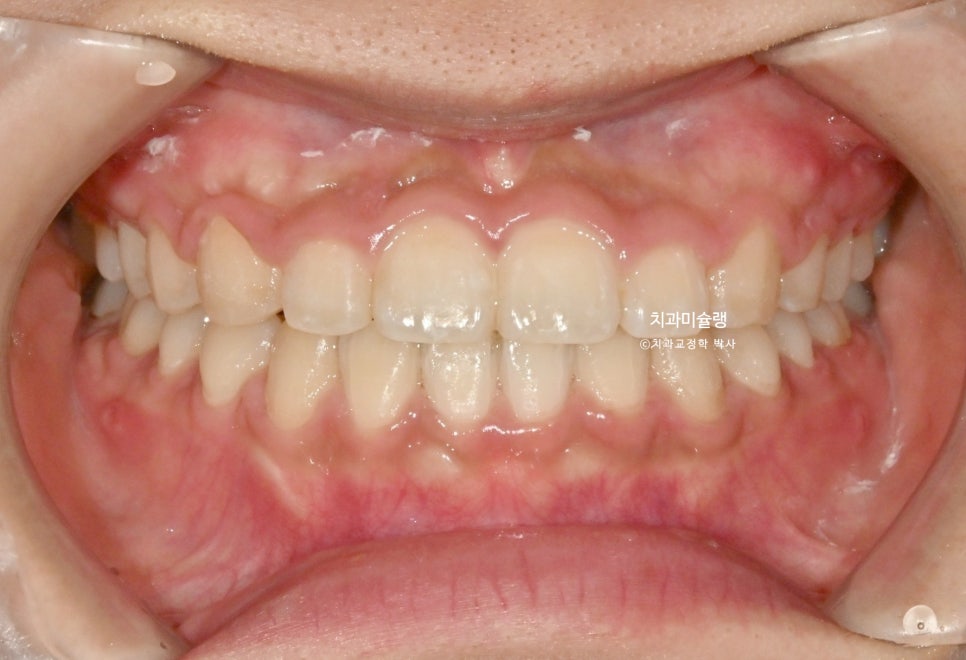

초진 당시 상황

작년 겨울, 앞니 벌어짐과 약간의 돌출감 때문에 오신 환자분입니다.

중심선 불일치, 앞니 벌어짐이 보입니다.

위 앞니가 뻗쳐있고 튀어나와있네요.

작은어금니를 발치할 정도의 돌출은 아니라 비발치 돌출입 교정 권유드렸습니다.

더불어 아래턱을 자가회전 시켜 하관을 짧게 만들고, 무턱처럼 보이는 턱끝도 개선하기 위해 상악 전체치열 후방이동과 동시에 함입도 하기로 합니다.